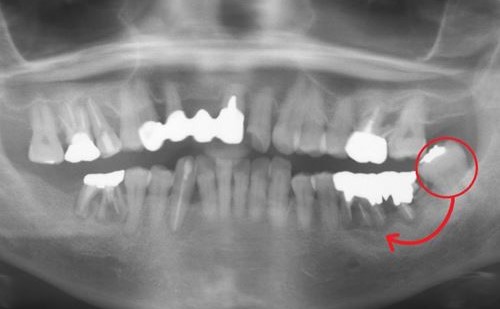

自家歯牙移植用レプリカ症例2-1

術前画像

自家歯牙移植用レプリカ症例2-2

右上7番抜歯